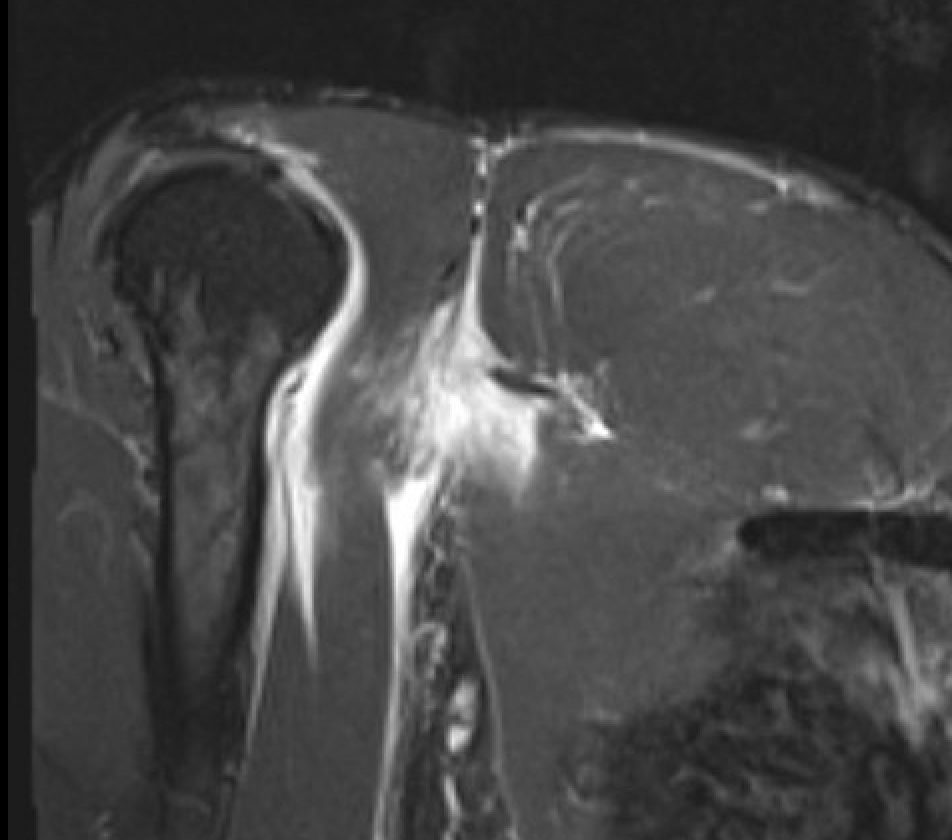

Coronal T2 Right shoulder demonstrating tendon avulsion of both sternal and clavicular heads